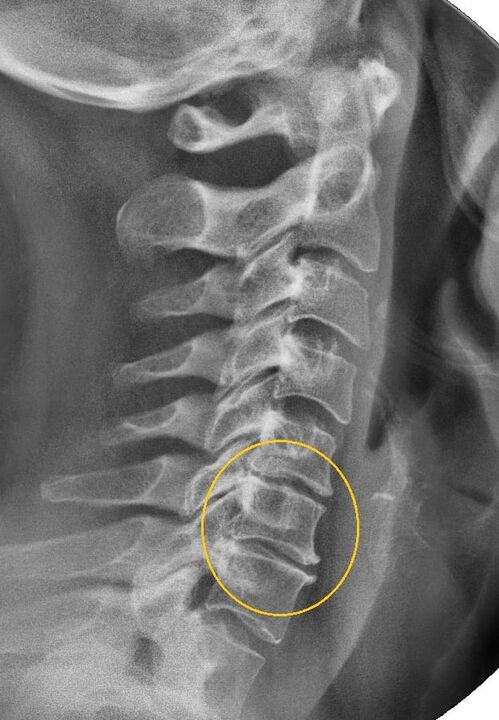

Das aussagekräftigste diagnostische Verfahren ist das Röntgen. Pathologien 1. Grades entsprechen dem 1. oder 2. radiologischen Stadium. Die resultierenden Bilder zeigen typische Anzeichen der Krankheit.

| Radiologische Stadien der zervikalen Osteochondrose ersten Grades. | Charakteristische Zeichen |

|---|---|

| Stufe 1 | Kleinere Veränderungen der Krümmung der Wirbelsäule im Halsbereich, die ein oder mehrere Segmente betreffen. |

| Stufe 2 | Leichte Verdickung der Bandscheiben, Verformung der Processus uncinatus, Aufrichtung der Lordose, geringfügige Wucherungen der Knochenstrukturen. |